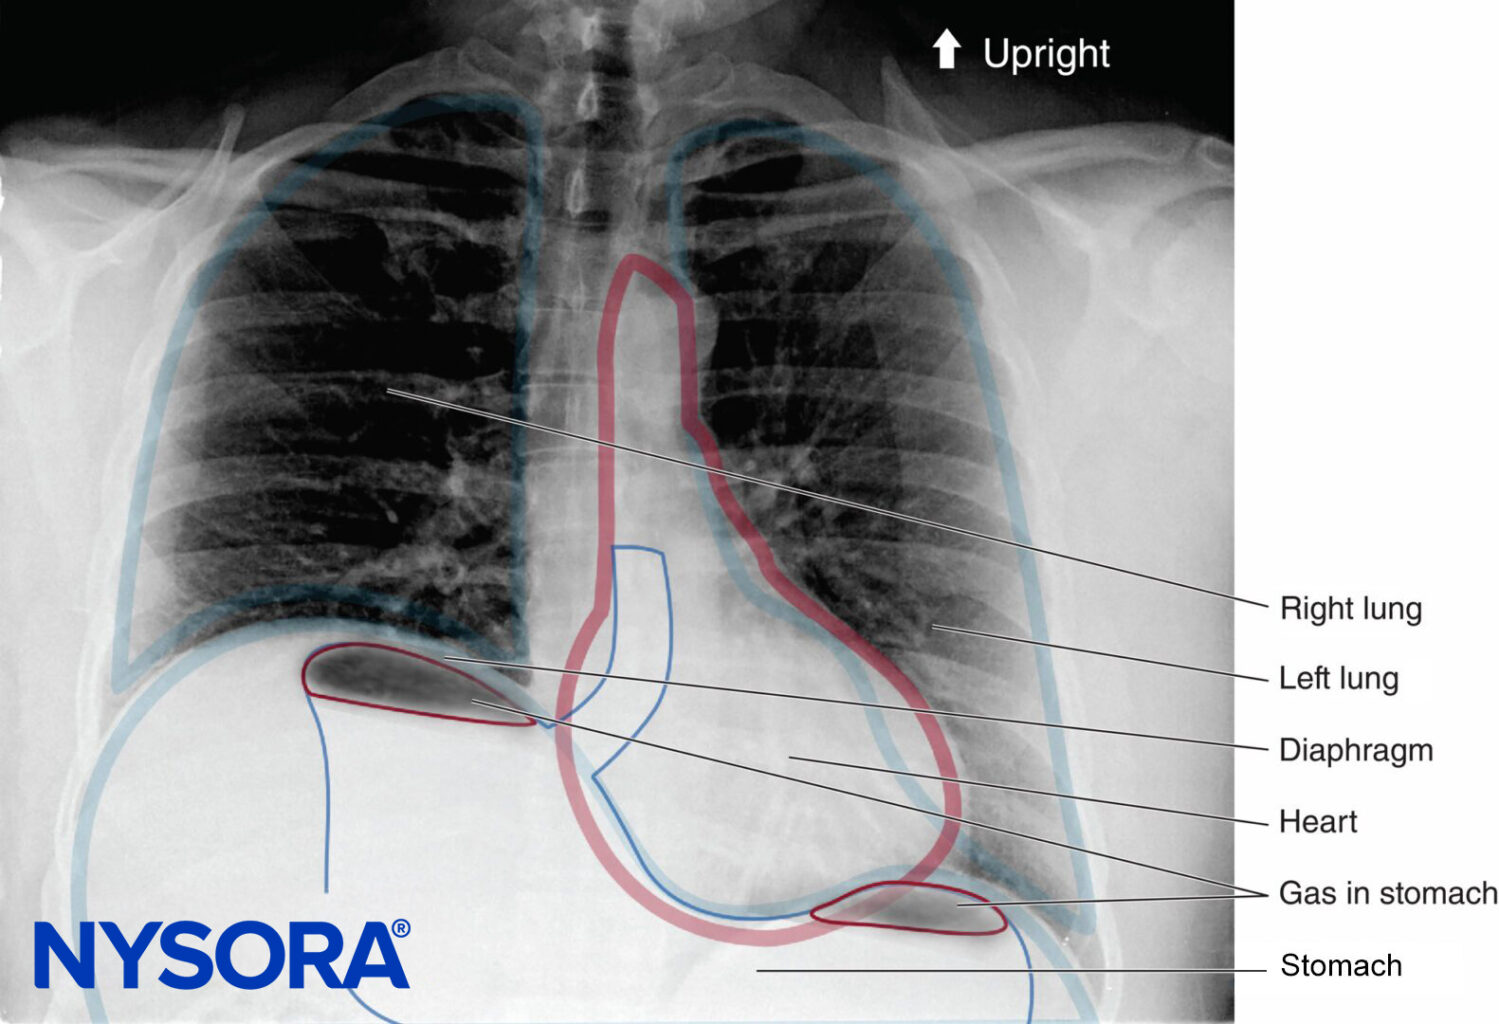

In the absence of rare complications such as pneumothorax, any alterations in respiratory mechanics seen with brachial plexus block are due primarily to phrenic nerve block and hemidiaphragmatic paralysis (Figure 1). This has been shown to occur in 100% of patients receiving interscalene block when performed without ultrasound guidance and using between 34 and 52 mL of local anesthetic. When diaphragmatic paresis occurs, there is an associated 27% reduction in both FVC and FEV1. While the clinical significance of this reduction in healthy patients is not entirely clear, it may be useful to risk-stratify patients about to undergo interscalene blocks as one would a patient undergoing lung resection. In other words, ask the question, “Will this patient tolerate a periopera-tive FEV1 reduction of 27%?”

FIGURE 48-1. Upright chest radiograph of a patient who underwent a right interscalene brachial plexus block. Note the elevated right hemidiaphragm.